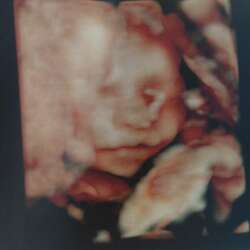

Wij hebben nog een zoontje van 7 en verwachten half april onze baby.